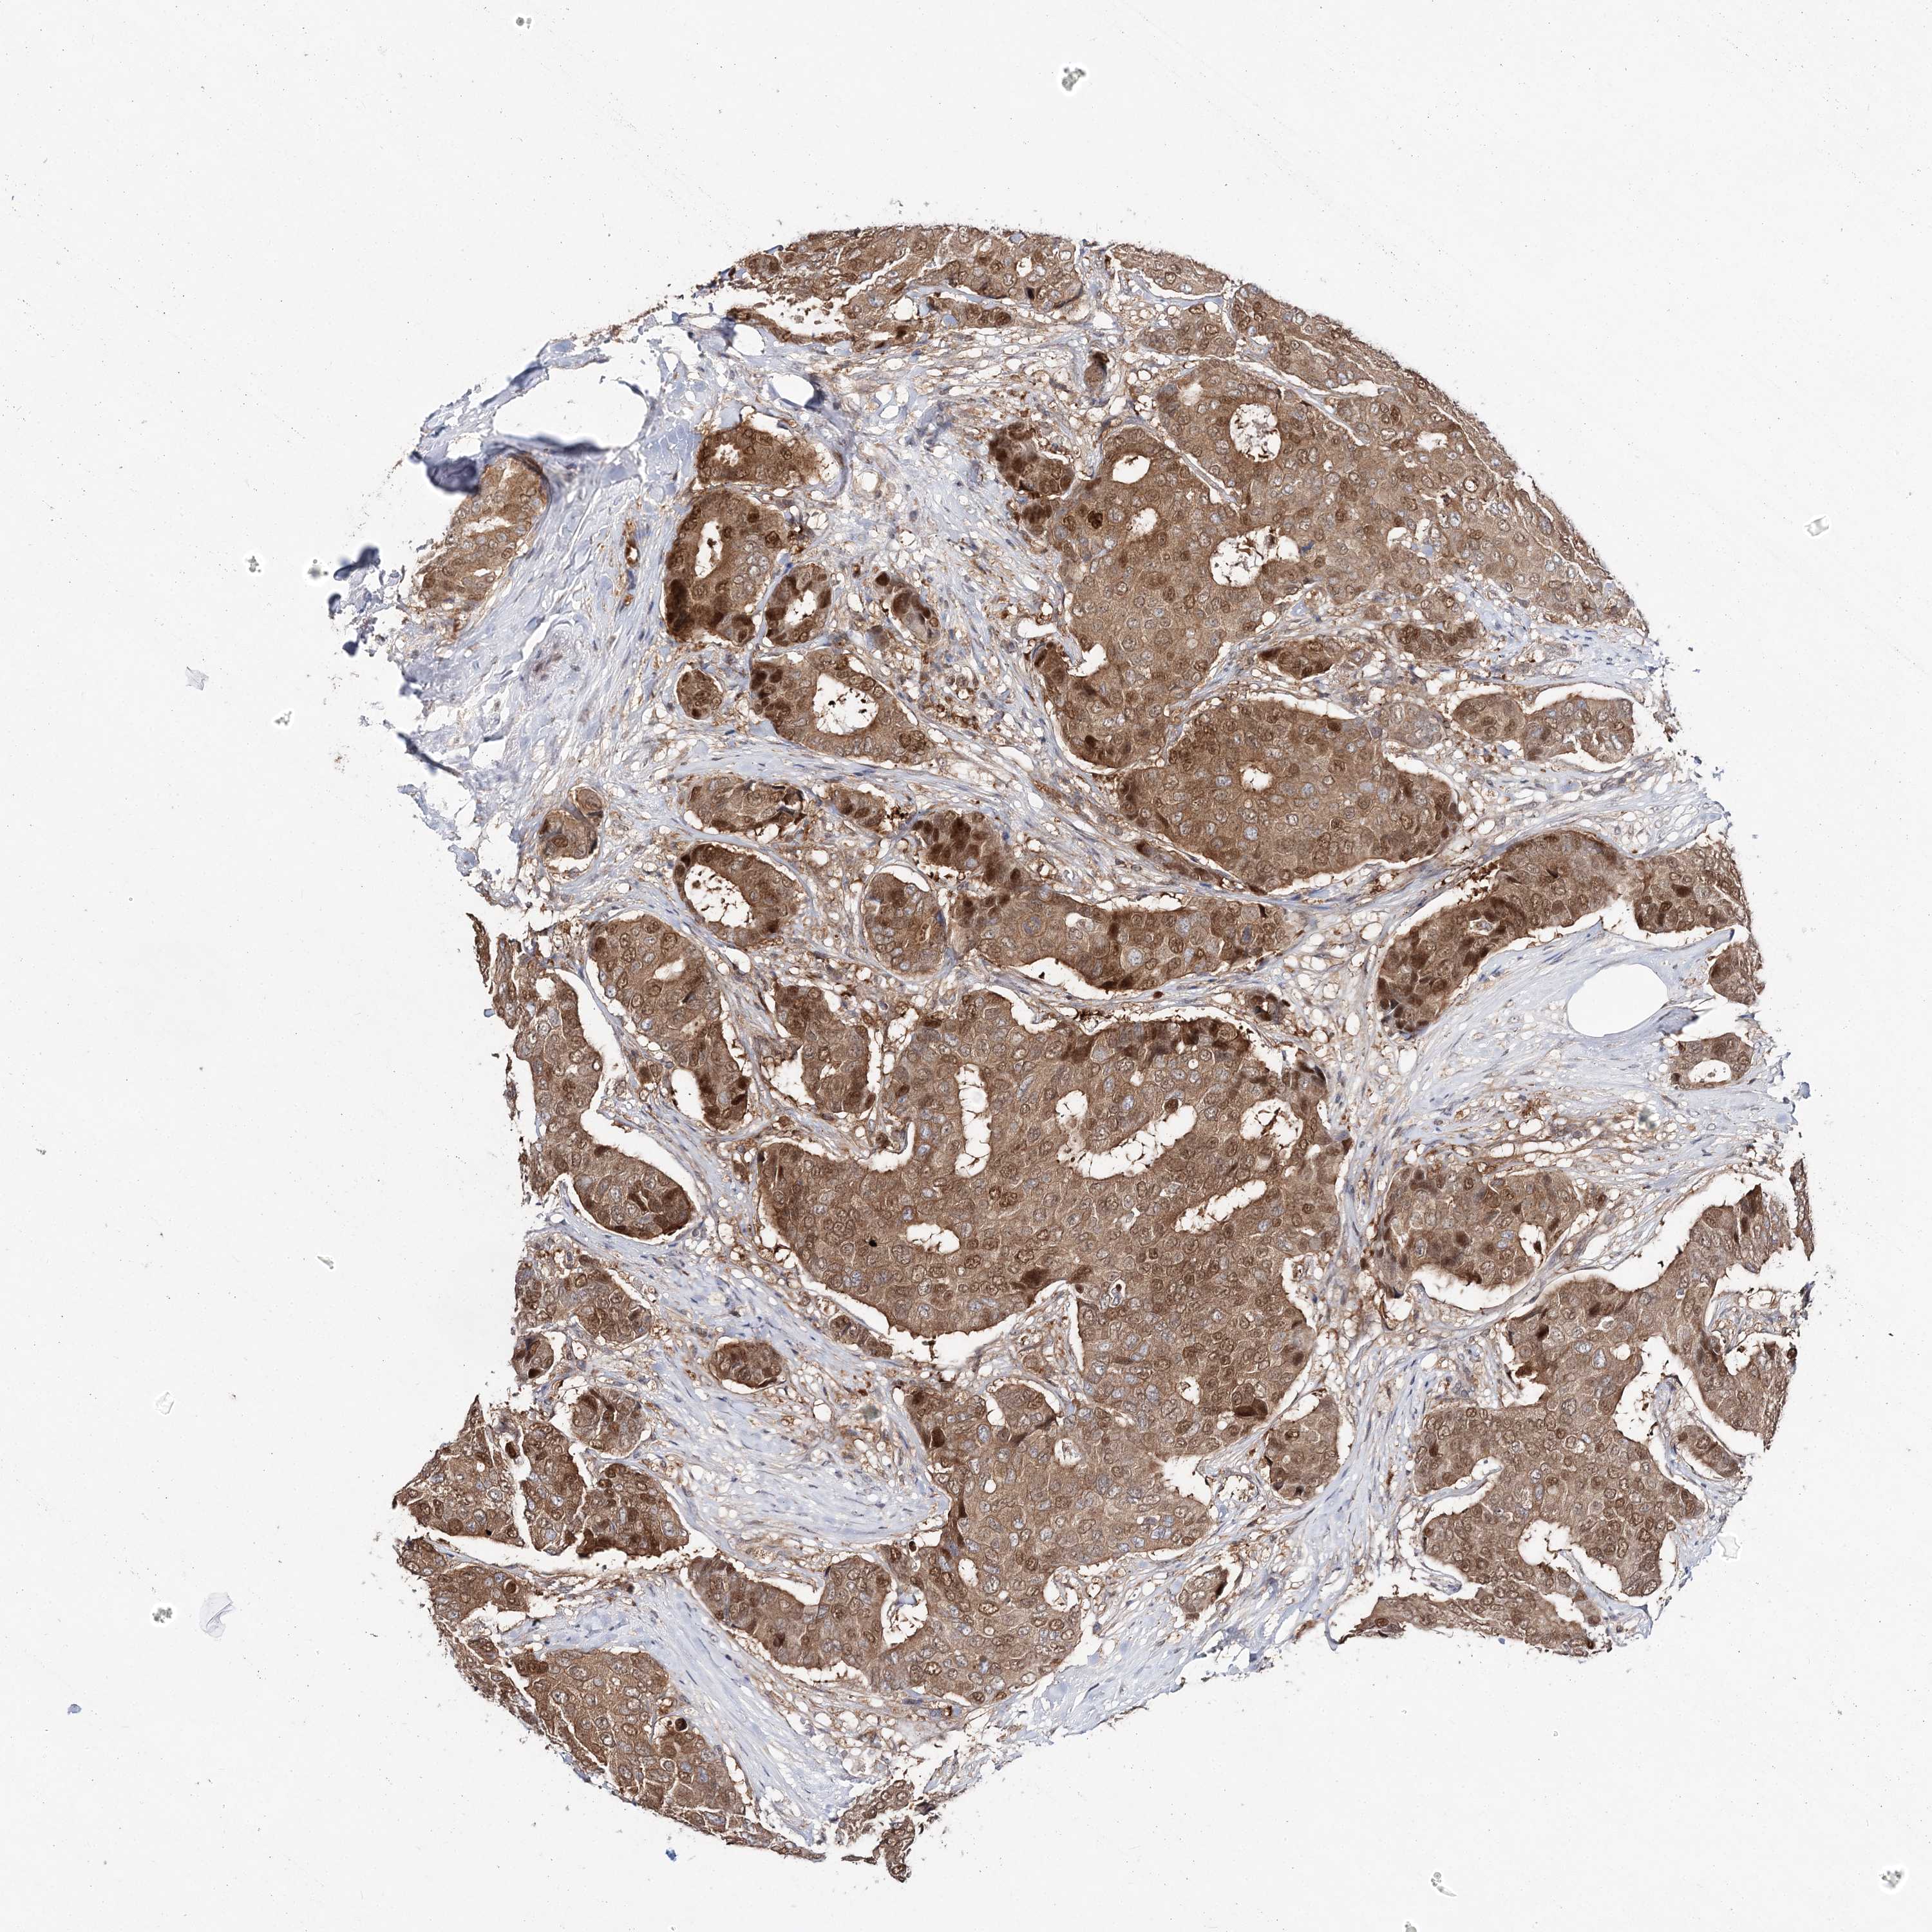

CANCER BREAST CANCER Show tissue menu

BRCA TCGA BRCA VALIDATION PROTEIN EXPRESSION